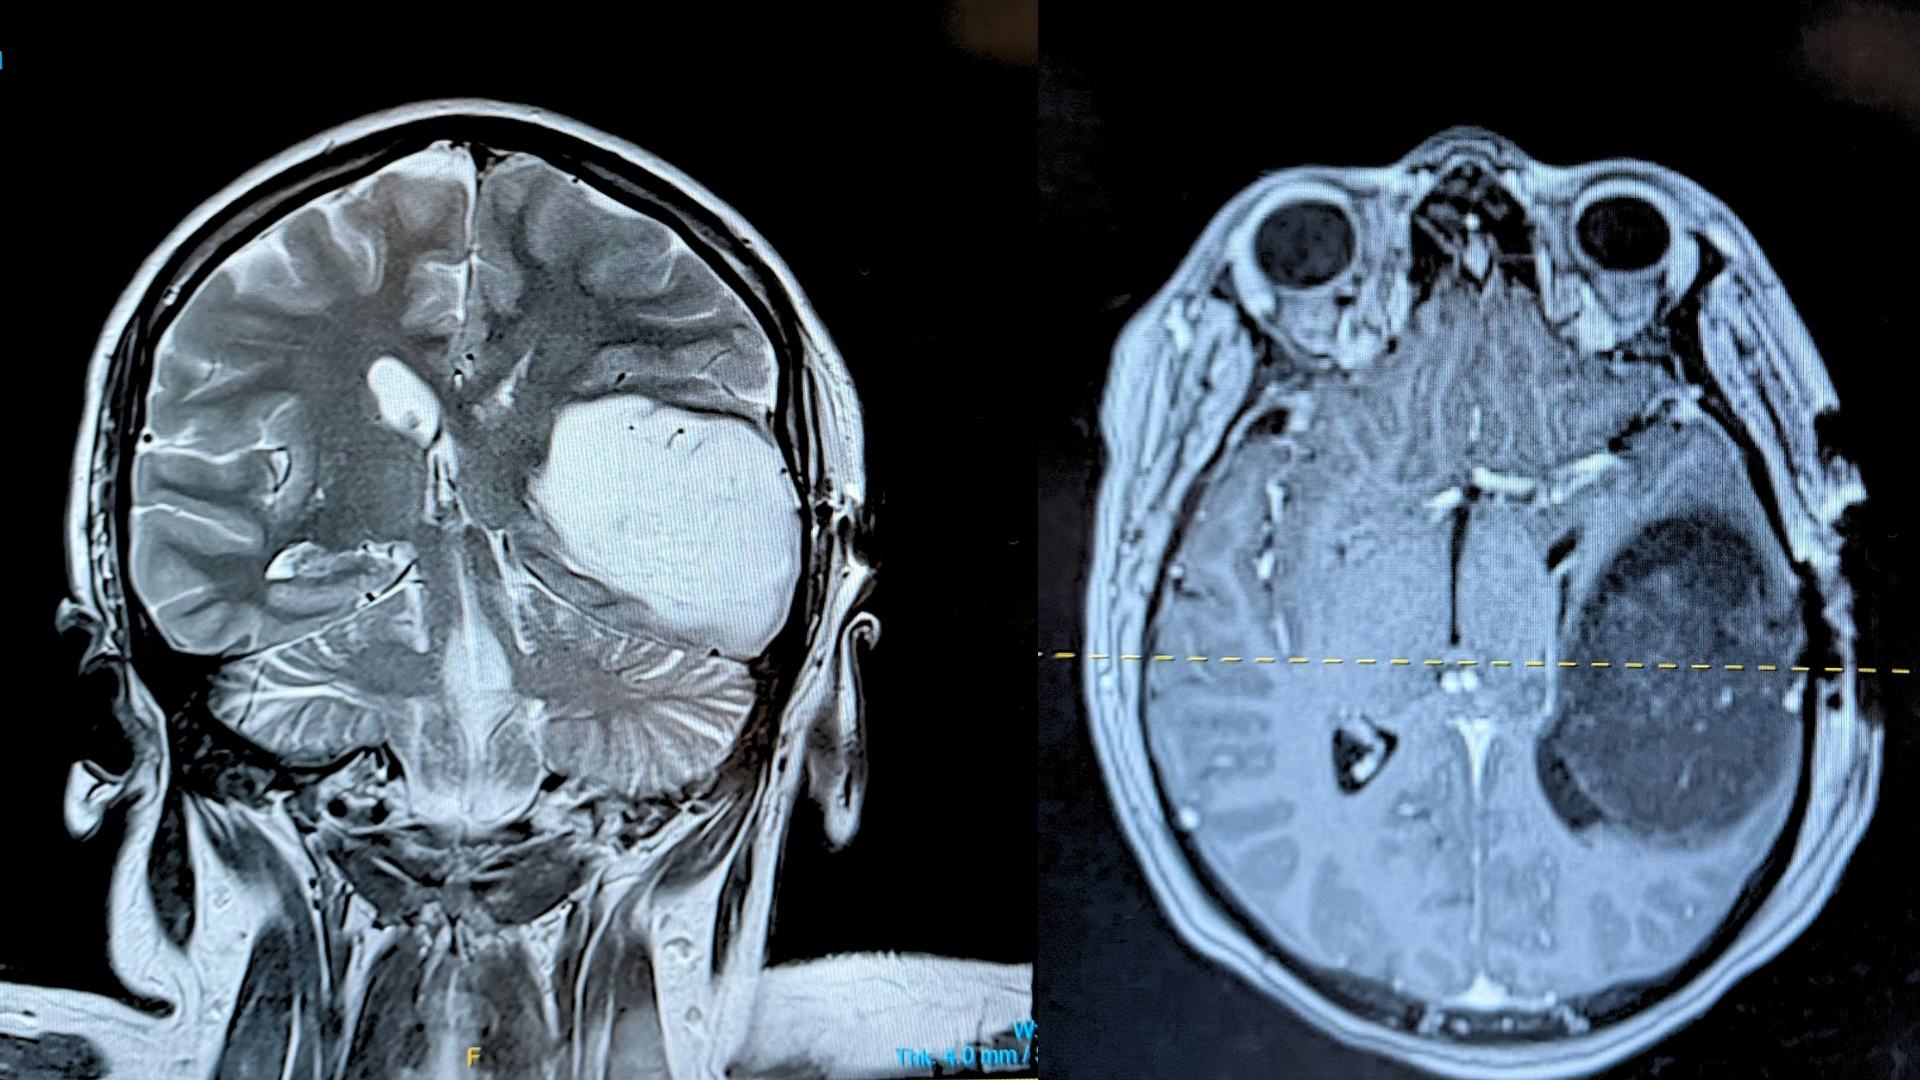

The scan revealed a large mass in the left temporal lobe of her brain—so significant that it was causing a shift across the midline. She was immediately admitted to the Neuro ICU, where she spent the next five days undergoing further testing, including a brain biopsy. The preliminary biopsy results came back abnormal, confirming that the mass is brain cancer. We are currently waiting on the full results, which will determine the exact type and grade of the tumor and guide her treatment plan.